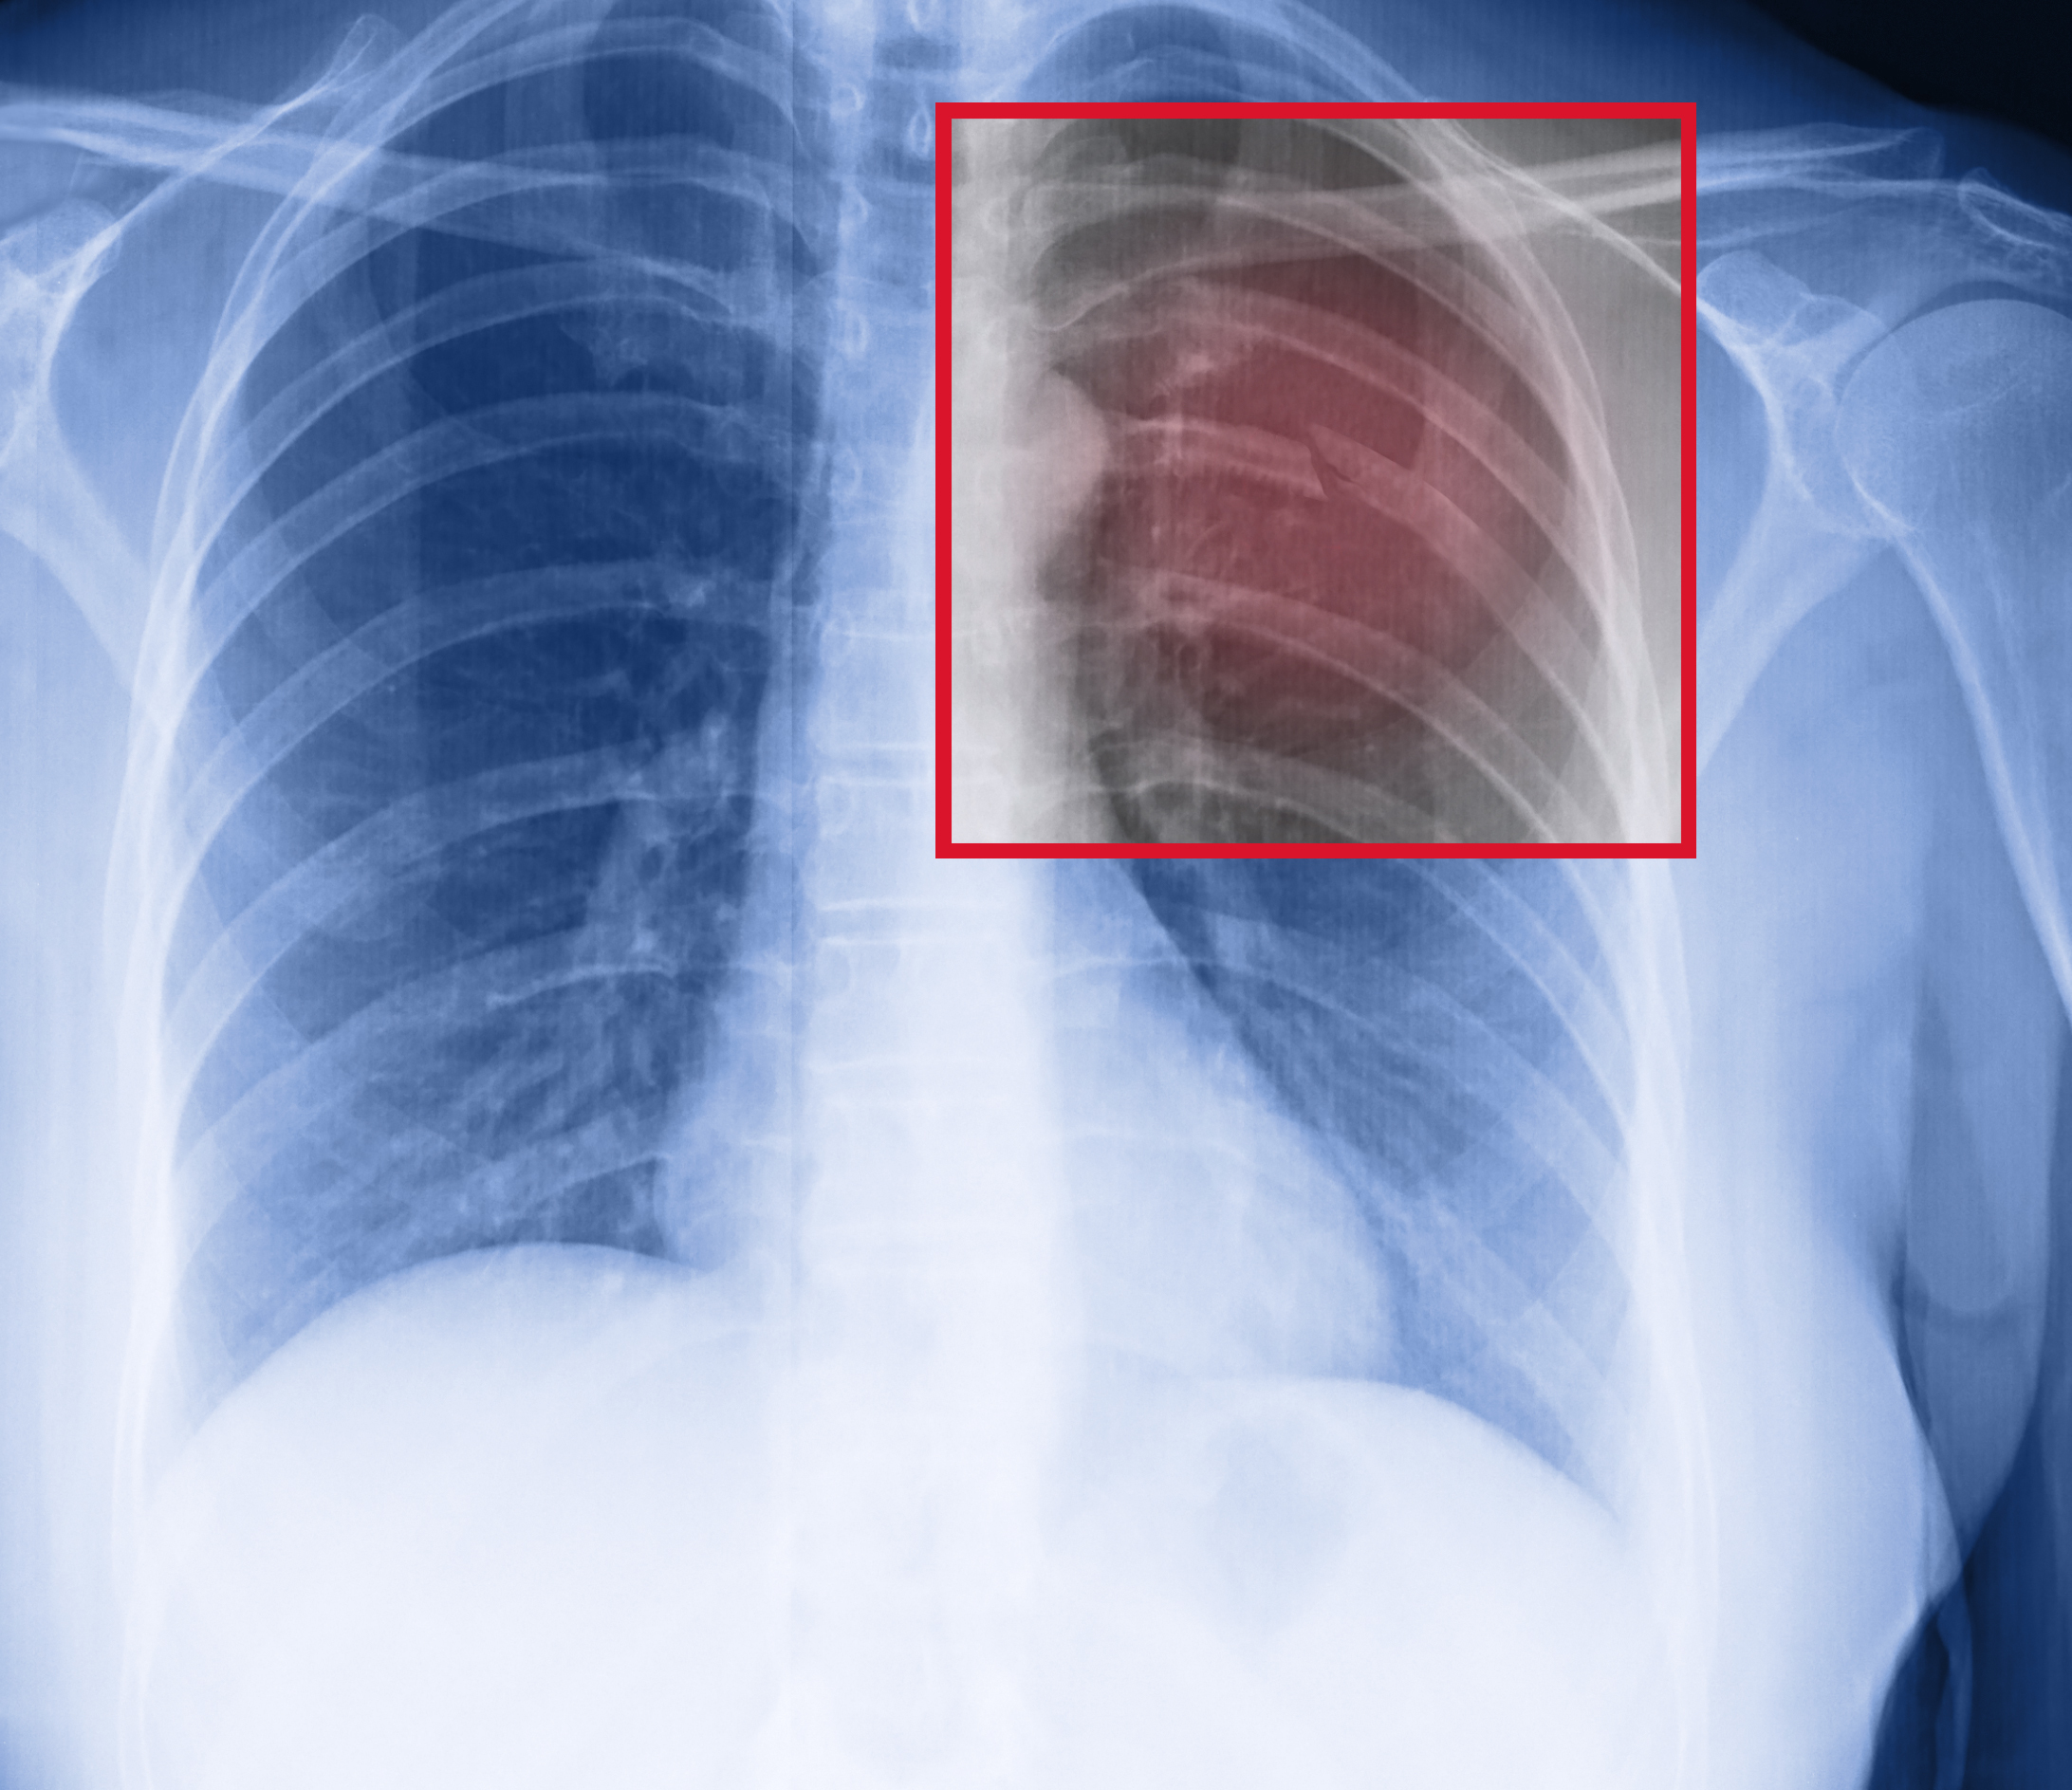

Травма органов грудной клетки на примере клинических случаев

Взгляд рентгенолога: травмы грудной клетки.

Мультиспиральная КТ в диагностике тупой торакальной и абдоминальной травмы